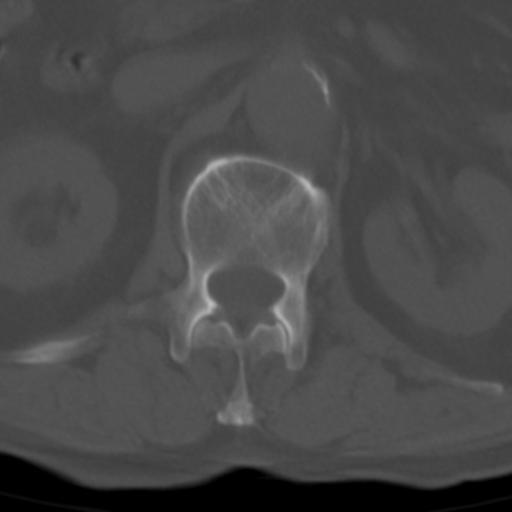

男性 82 主动脉夹层 请大家看看椎体是什么改变啊

腰椎退行性变,明显的骨赘形成,所指低密度灶为正常松质骨。